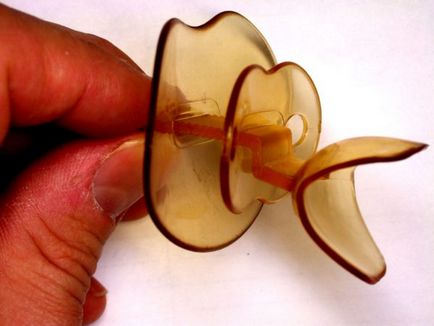

orrcsipeszek

Ez egy egyszerű és biztonságos eszköz. Segít a férfiak, akiknek a horkolás okozta szűkülete az orrjáratok, valamint azokat, akik szenvednek a krónikus nátha.

Különböző problémák a garat készülék nem hoz sok jó, ebben az esetben, hogy segítsen betétet vagy intraorális implantátumokat. Egy kis szúrás a torok lehet egészíteni klip permet horkolás, duó hatékonyabb lesz.

Egyes esetekben, a golyók vannak felszerelve mágnesek, növelve a jótékony hatása a készülék. A klip kerül az este, akkor lehet alkalmazni, sokáig.

Ellenjavallat lehet az alvási apnoe és súlyos eltért septum. Ár függ a gyártó és a tartomány 180-1200 rubel.